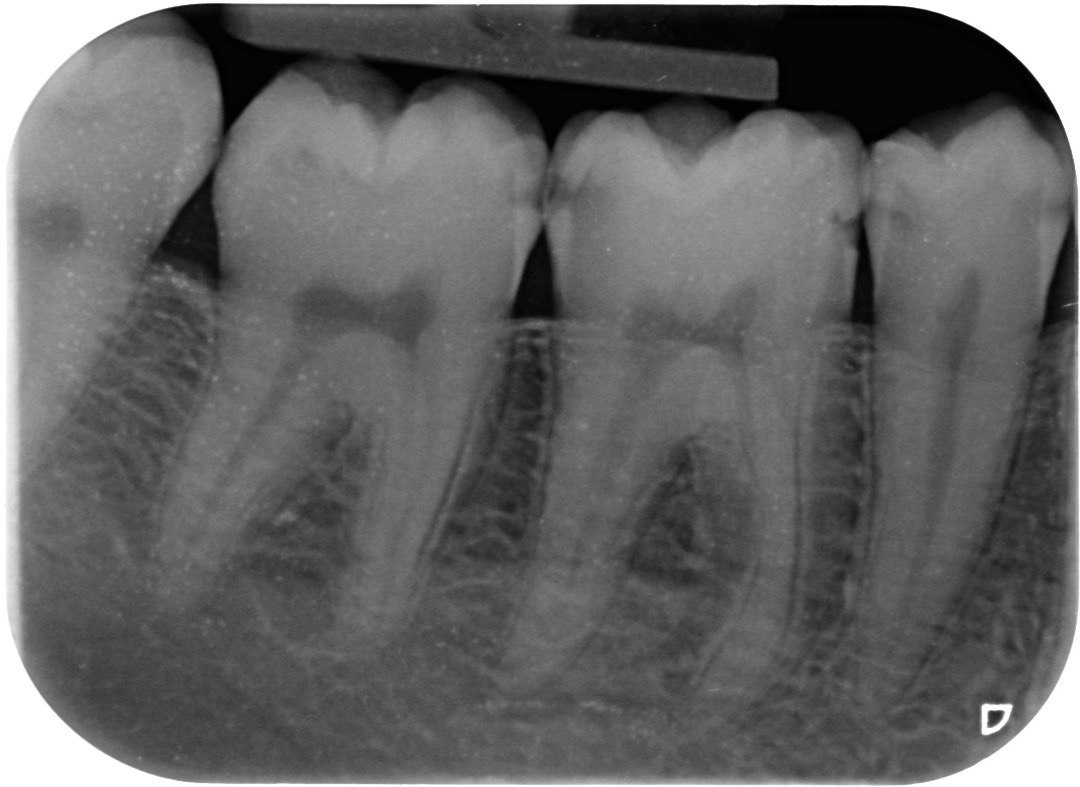

1. What surface require restoration?